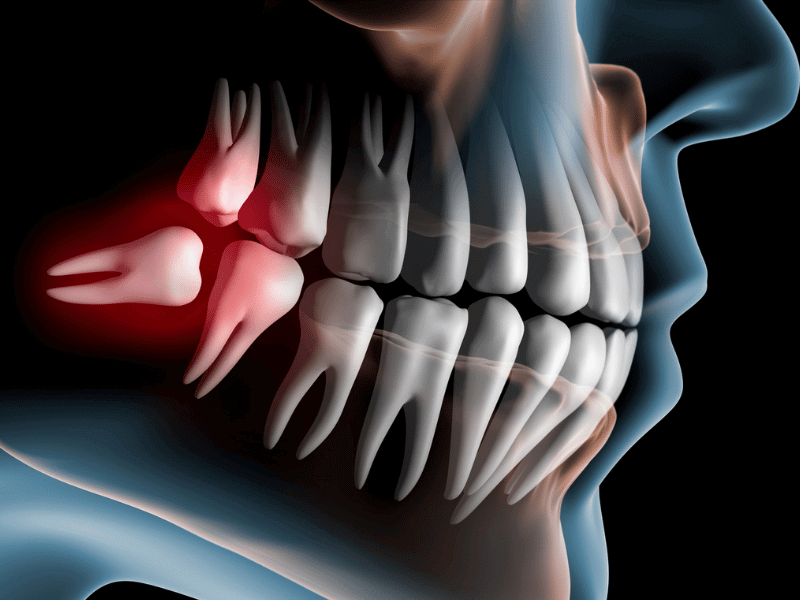

Impacted Third Molar

Illustration of Impacted Wisdom Teeth

Your wisdom teeth, also known as third molars, are the last set of teeth to emerge, typically during early adulthood. However, these teeth often lack sufficient space to erupt properly, leading to impaction – a condition where they become trapped beneath the gum line or adjacent teeth. At Enamel Elegance, our skilled oral surgeons specialize in the safe and effective removal of impacted wisdom teeth, alleviating discomfort and preventing potential complications.

Wisdom tooth removal, or impacted third molar disimpaction, may be necessary to address impacted teeth and prevent potential complications if you have: